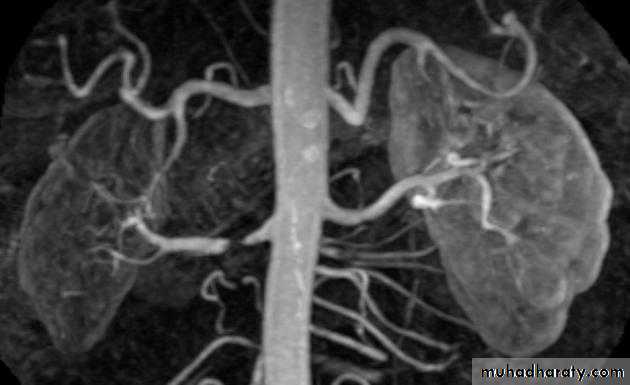

MRA showed a high-grade stenosis of the proximal right renal artery. The right kidney was markedly smaller but smoothly marginated. Parenchymal enhancement of the right kidney was delayed.